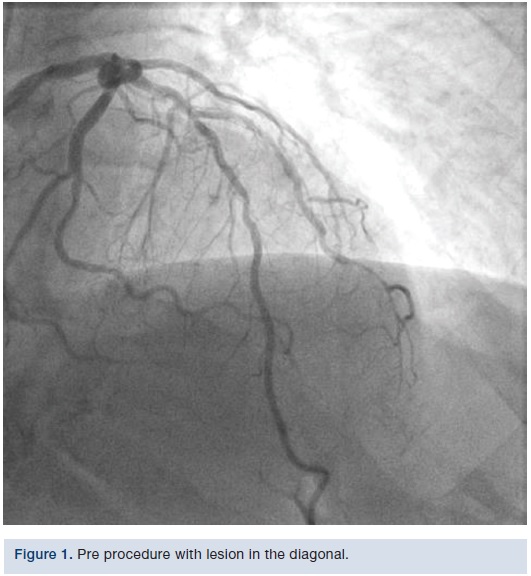

The LAD was patent in its proximal portion. The mid LAD gave rise to the diagonal (D)1, which had a stent going from the ostium to the mid portion. In some views, it appeared as though part of the struts could be in the LAD itself. The distal edge of the stent had a 95% to 99% restenosis and in-segment restenosis. Distally, the vessel was small and had a long 80% stenosis. The LAD itself had borderline 50% stenosis after the diagonal and then a patent stent. The remaining LAD appeared widely patent.